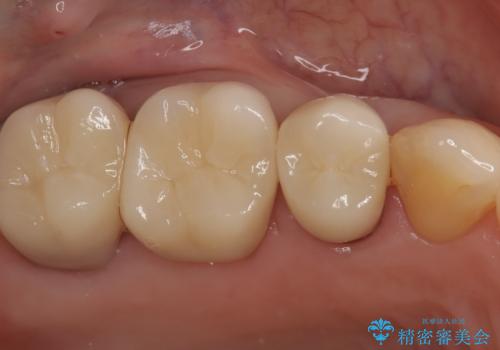

繰り返すプラスチックの欠けを解消。広範囲の修復に適したセラミッククラウン

担当医 河口智英

欠けやすい大きなプラスチック充填から、耐久性の高いセラミッククラウンへ